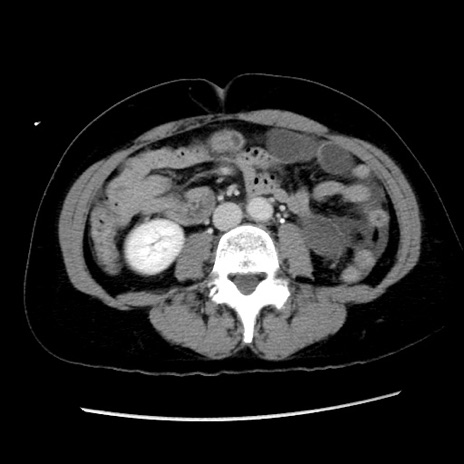

症例10(横断像)

【症例】 50歳代女性

【主訴】 腹痛

【現病歴】前日生レバーを食べた。今朝に排便あり。 昼前に突然発症の腹痛を生じ、当院救急外来を受診した。

【身体所見】 意識清明、腹部:平坦、軟、下腹部やや左を中心に圧痛・反跳痛あり、筋性防御あり

【データ】WBC 7800、CRP 0.07